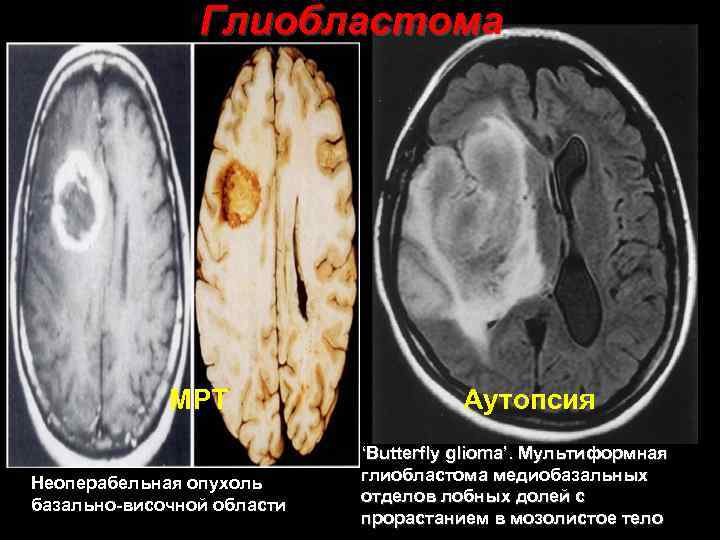

Глиобластома МРТ Неоперабельная опухоль базально височной области Аутопсия ‘Butterfly glioma’. Мультиформная глиобластома медиобазальных отделов лобных долей с 37 прорастанием в мозолистое тело